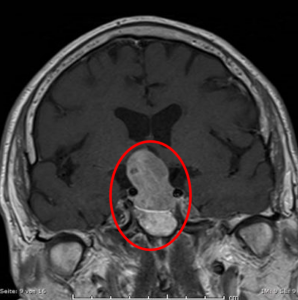

Beispiele von großen Hypophysenadenomen